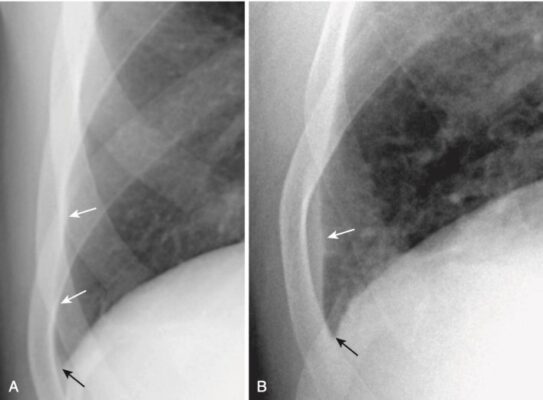

Tràn dịch màng phổi lớp mỏng (laminar Effusions)

- Tràn dịch màng phổi lớp mỏng là một dạng tràn dịch màng phổi trong đó chất lỏng tạo một đậm độ hình dải mỏng dọc theo thành ngực bên, đặc biệt là gần góc sườn hoành. Góc sườn hoành bên có xu hướng giữ nguyên góc nhọn với tràn dịch màng phổi lát mỏng, không giống như góc tù xảy ra với tràn dịch màng phổi thông thường.

- Tràn dịch lớp mỏng hầu như luôn luôn là kết quả của tăng áp lực tâm nhĩ trái, như trong suy tim sung huyết hoặc thứ phát sau bệnh lý ác tính lan truyền qua đường bạch huyết. Chúng thường không chảy tự do.

- Có thể nhận ra chúng bằng dải tăng đậm độ ngăn cách phổi chứa đầy khí với bờ trong của các xương sườn ở đáy phổi trên phim chụp X quang ngực thẳng. Ở những người khỏe mạnh, một lá phổi được thông khí phải trải rộng đến bên trong của mỗi xương sườn tiếp giáp (Hình 15).